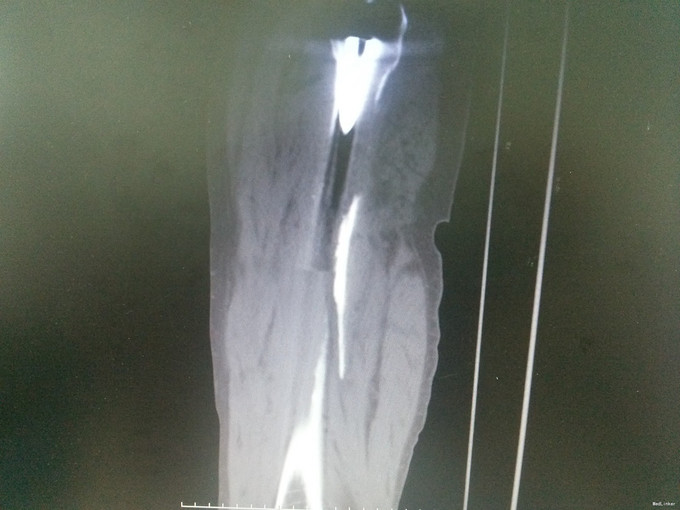

诊断:假体周围骨折(左股骨假体柄周围骨折);高血压病;脑梗死后遗症;陈旧性肺结核 治疗:手术治疗[左侧股骨假体取出术+左侧股骨假体周围骨折切开复位钢板钢缆内固定术(zimmer)+左侧股骨假体置入术(MP,Link)] 术中探查及处理:股骨大粗隆崩裂,骨折线自近端向远端延伸至股骨中段,呈螺旋形,骨折块粉碎,移位明显。骨折断端可见淤血块。顺利取出假体柄后,复位骨折块,予复位钳临时固定后,予钢板钢缆(zimmer)加压捆扎。待骨折固定牢靠后,按照髋关节置换流程逐步扩髓,最后选择25omm长的14号假体(MP,Link)安装,36mm标准颈股骨头复位。测试各方向活动良好,松紧度合适。

讨论: 一、诊断:结合患者既往史及影像学表现,不难诊断。结合术中探查,骨折线延伸到假体柄以远的位置,假体松动。因此该假体周围骨折按温哥华分型属于C型。 二、治疗:手术治疗首选。患者既往基础病较多,结合入院检查检验评估病情后,认为患者手术耐受性可,故建议手术治疗。患者家属态度积极。 三、经验: 1.术前详细评估很重要。我们予CT平扫详细评估骨折状况,准备了足够长的假体和骨折内固定装置。平片显示髋臼假体良好,故未行髋臼翻修。 2.患者既往长期服用阿司匹林,凝血功能偏差,且因中风欠活动导致骨质疏松,预计术中出血量较多,因此术前准备自体血回输器,并备同型红细胞悬液。保证了充足的血容量。且术后积极加强补液,患者术后未出血失血性休克的不良反应。 三、反思:人工关节翻修代价极大,不仅对术者的水平是大的挑战,对患者的身体及经济更是一种非常大的挑战。 1.该患者基础病多,身体偏差,再次手术对身体创伤极大,手术并发症风险极高。 2.关节翻修需要特殊的假体及内固定装置,手术花费也巨大,普通家庭很难承担。 3.翻修手术出血多,手术时间长,感染率远高于初次关节置换,住院时间长。 该患者中风史,手脚行动不利,于我院行初次全髋关节置换后回家疗养,不慎跌倒致假体周围骨折,跟我们没有做好宣教工作有一定关系。这个病例,让我们更加重视患者出院时防跌倒、防脱位等宣教工作。